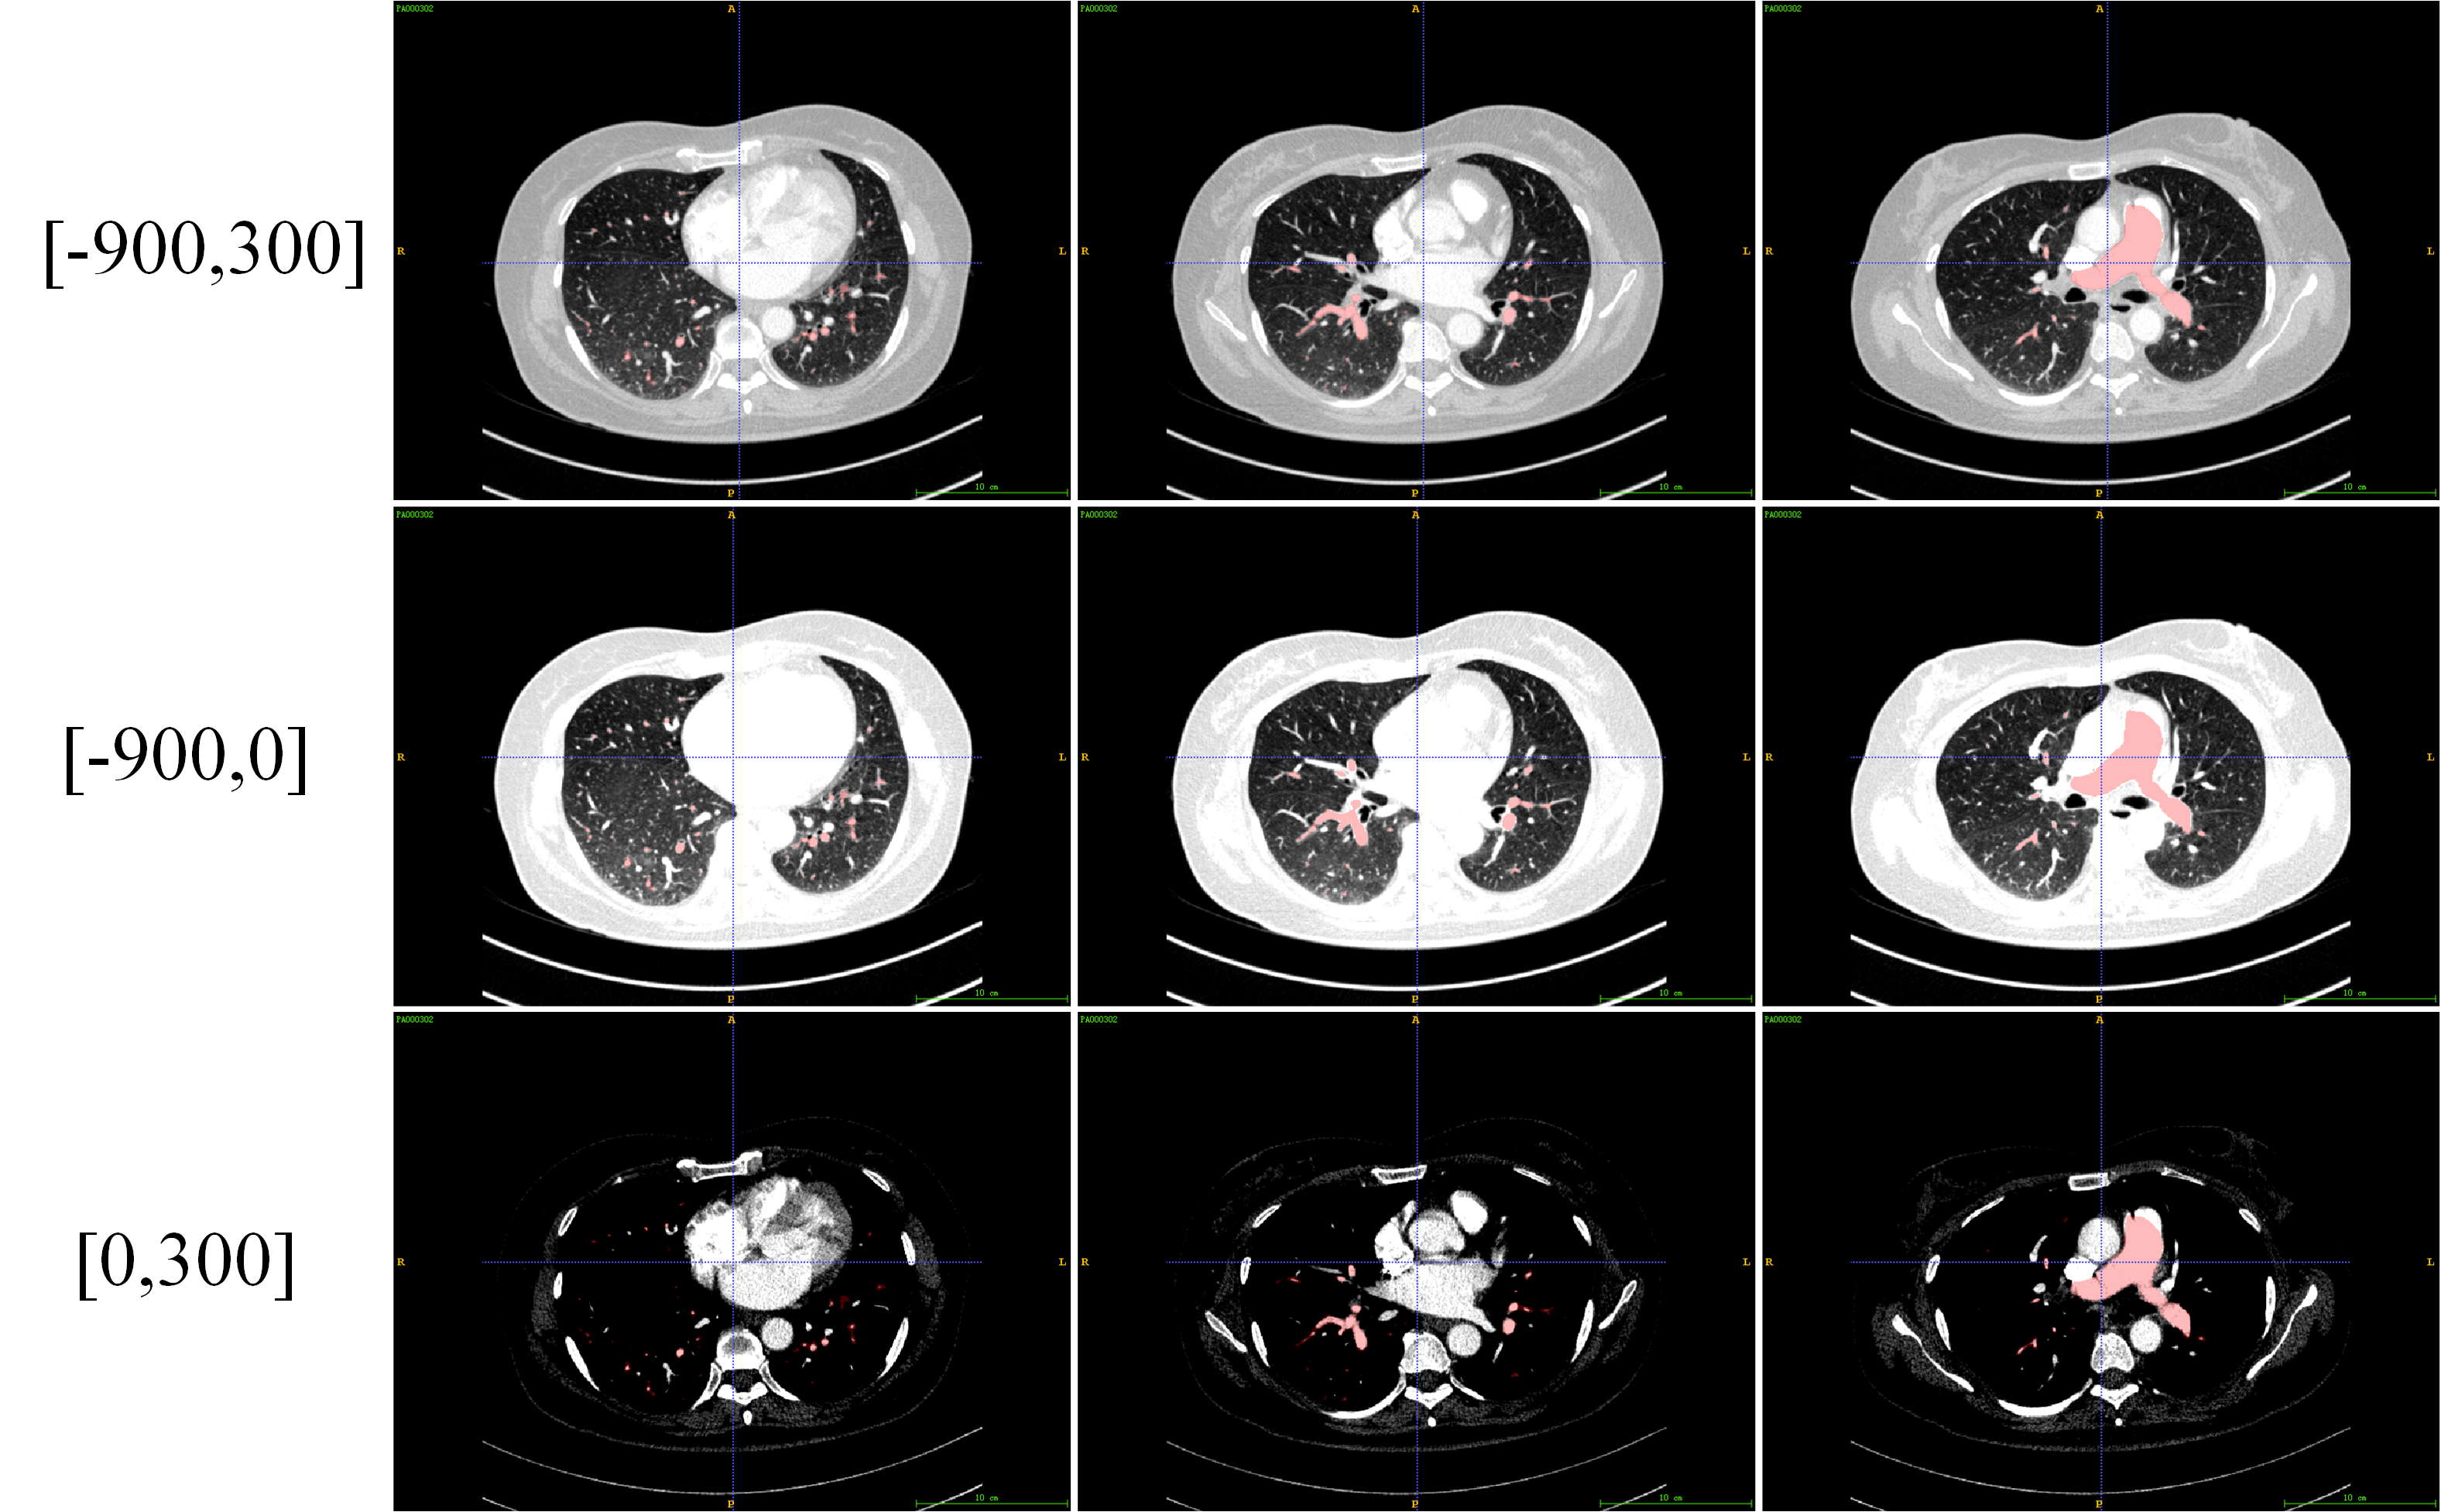

This is the technical report of the 9th place in the final result of PARSE2022 Challenge. We solve the segmentation problem of the pulmonary artery by using a two-stage method based on a 3D CNN network. The coarse model is used to locate the ROI, and the fine model is used to refine the segmentation result. In addition, in order to improve the segmentation performance, we adopt multi-view and multi-window level method, at the same time we employ a fine-tune strategy to mitigate the impact of inconsistent labeling.